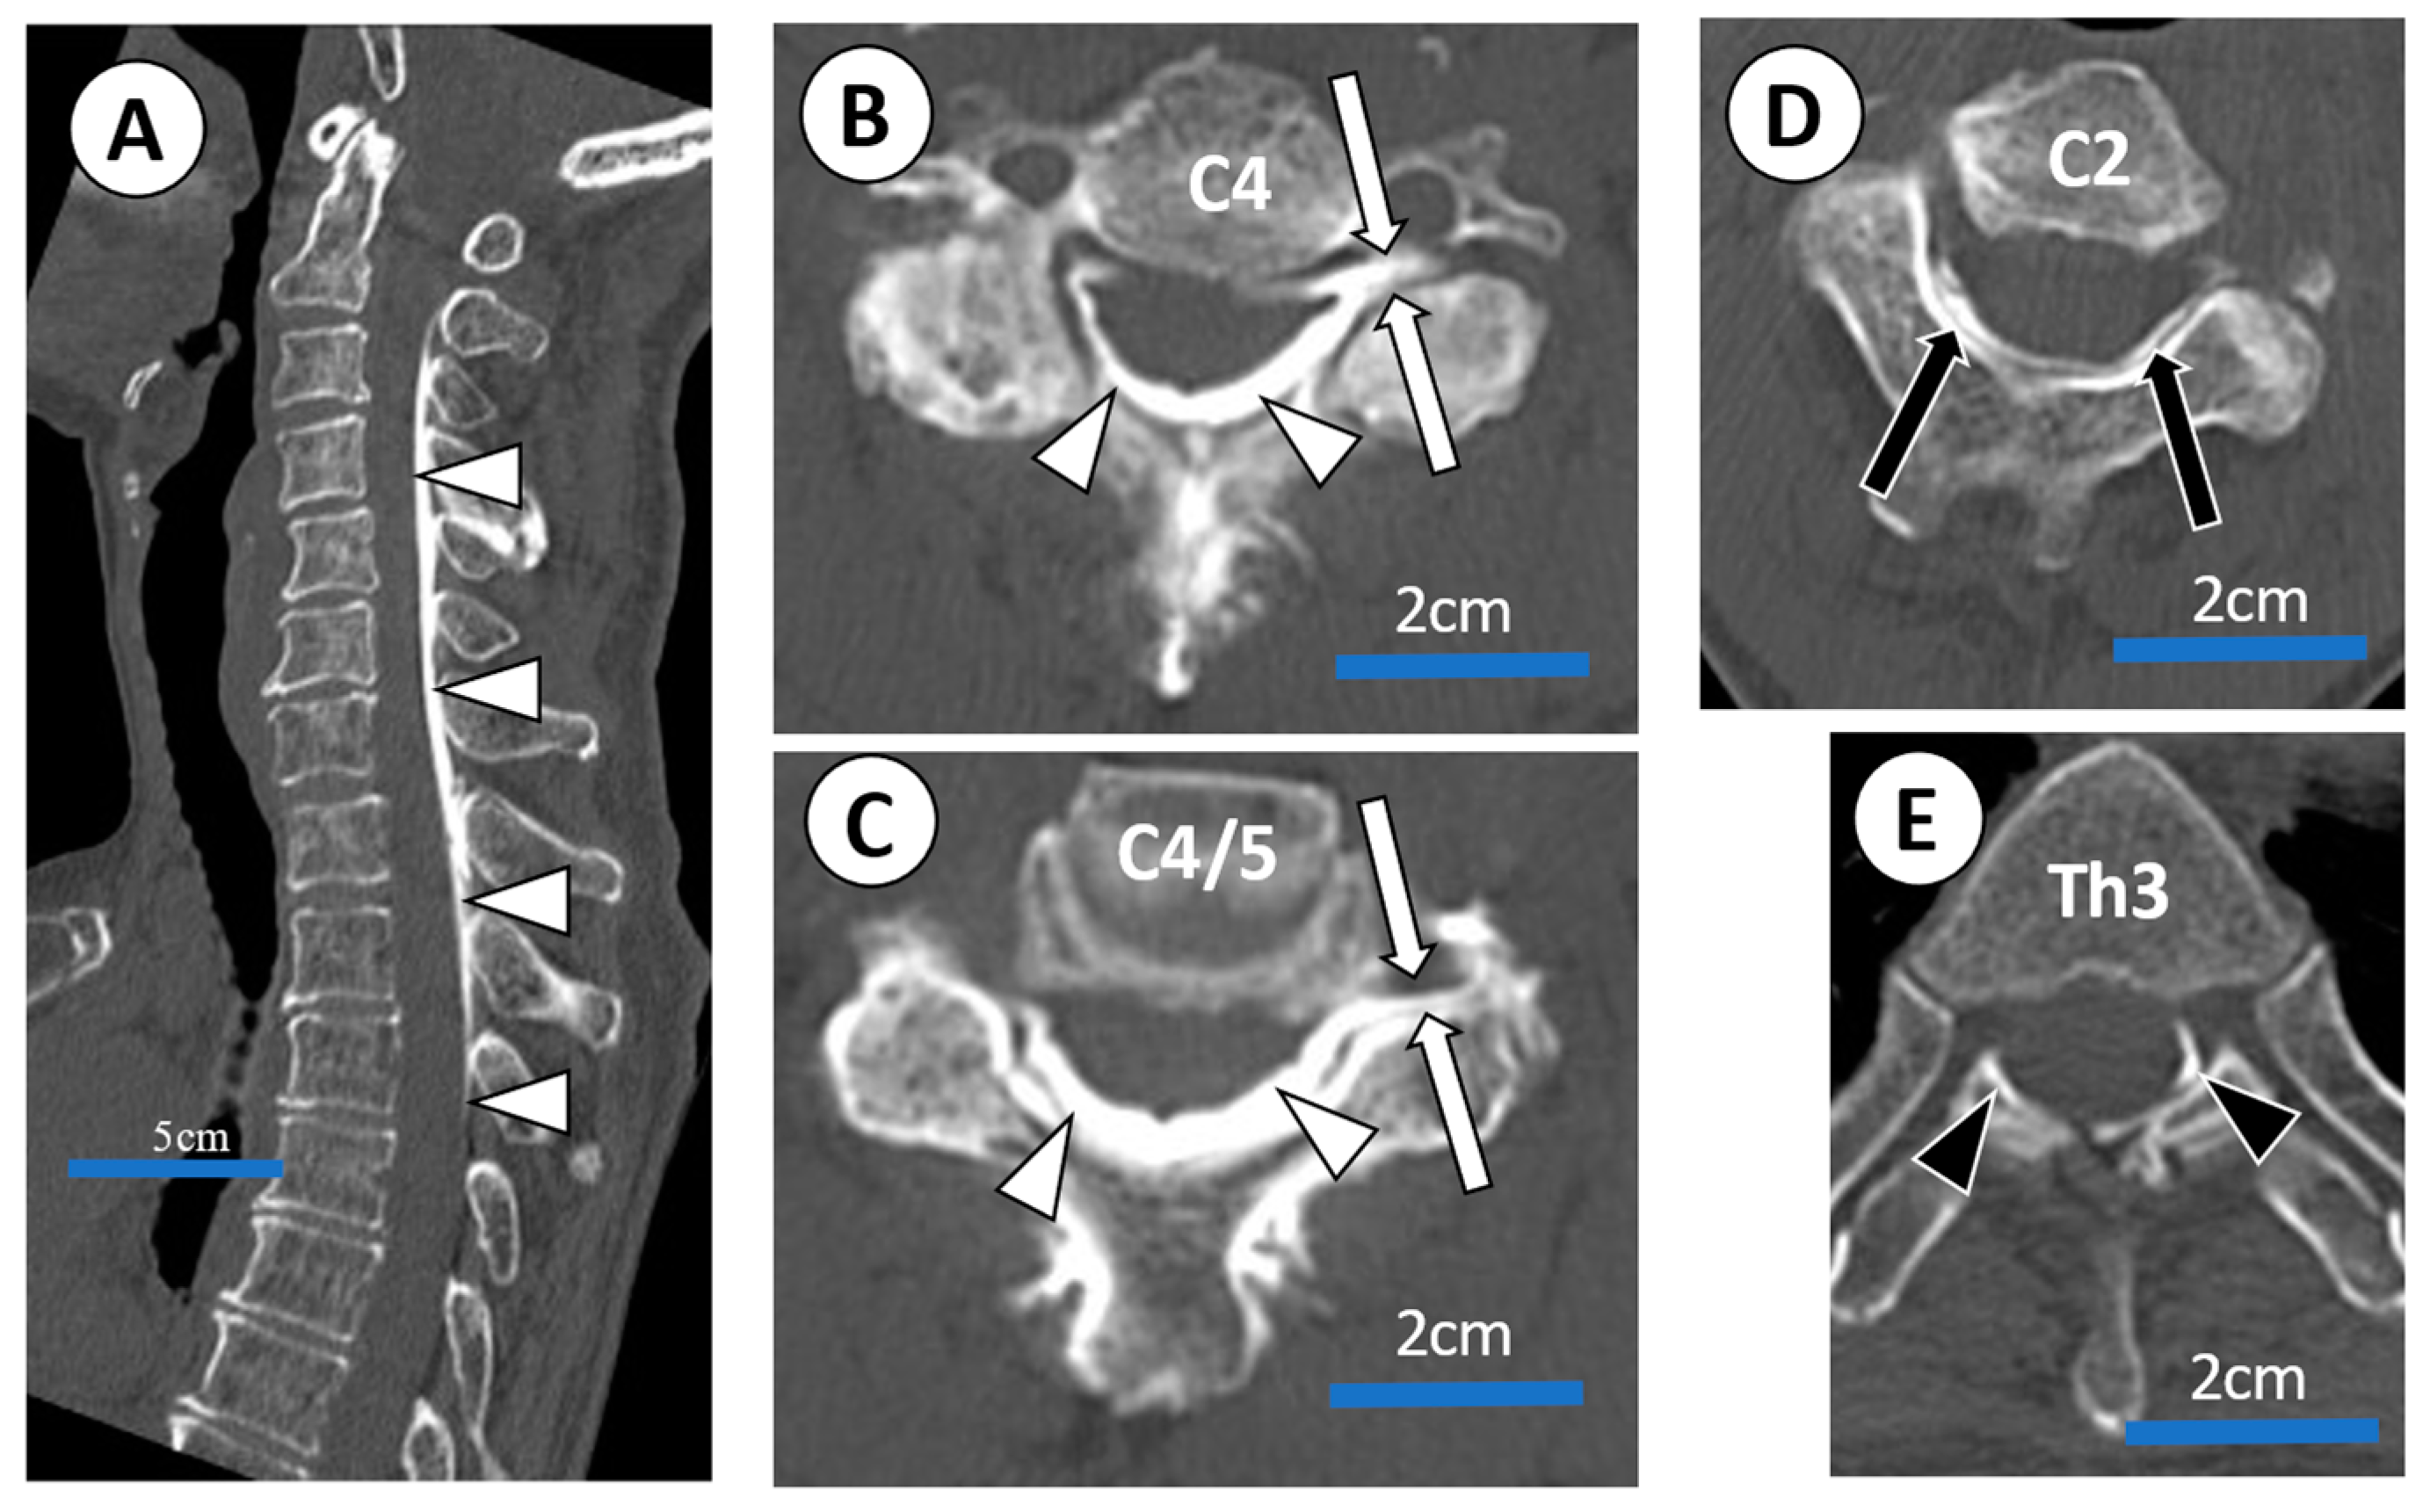

3.1.1. Case 4

3.1.2. Case 5

3.1.3. Case 9